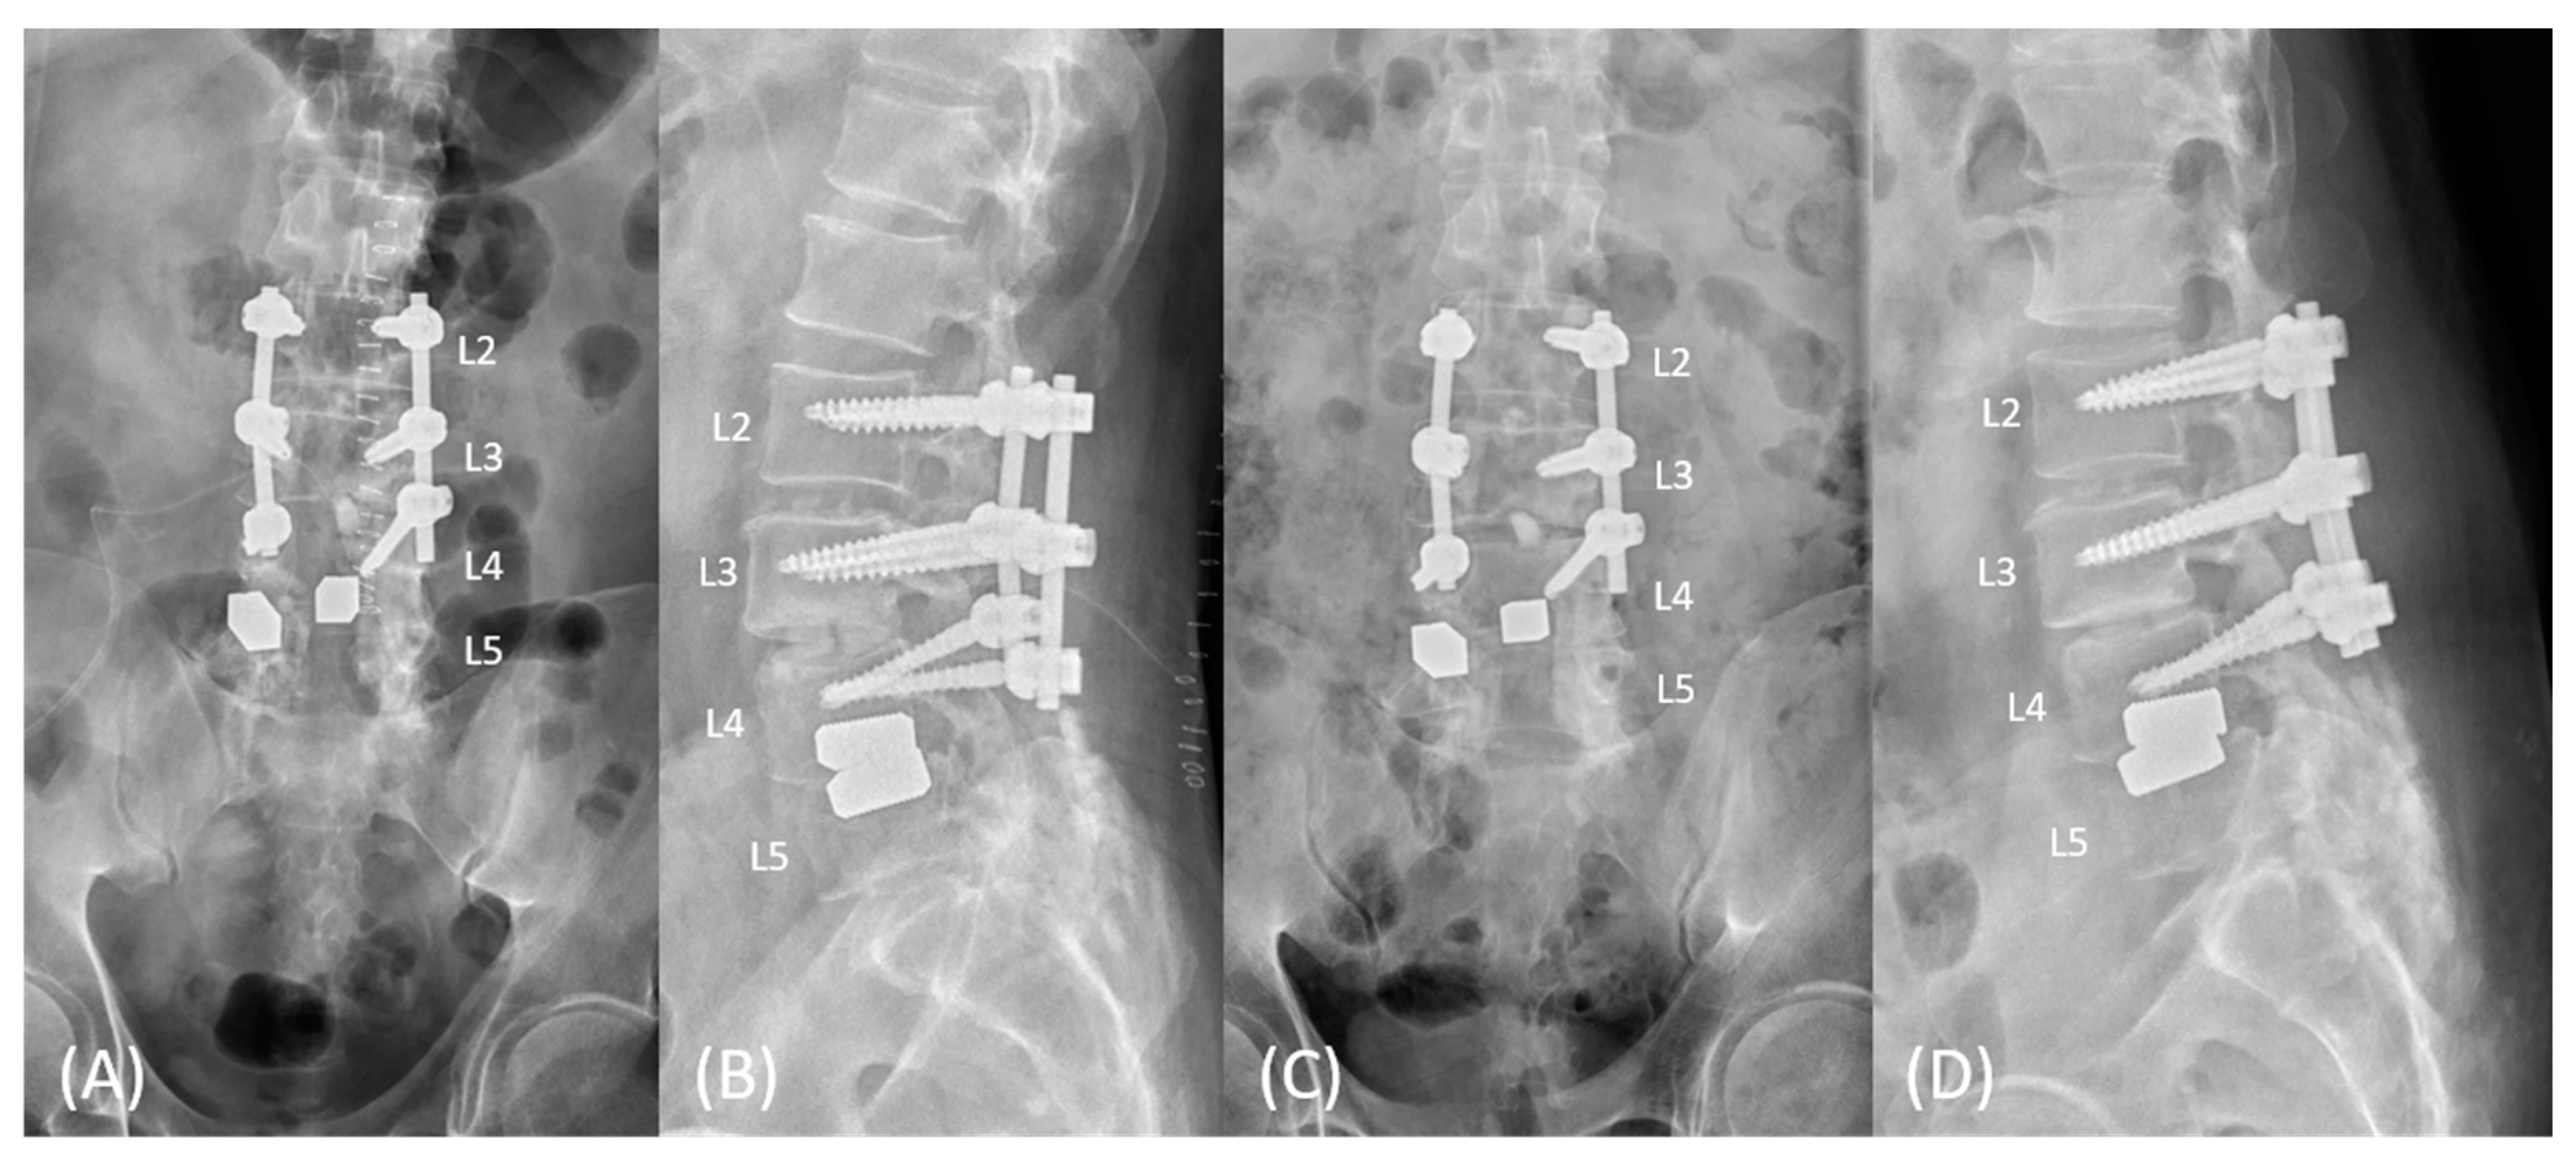

2. Case Presentation